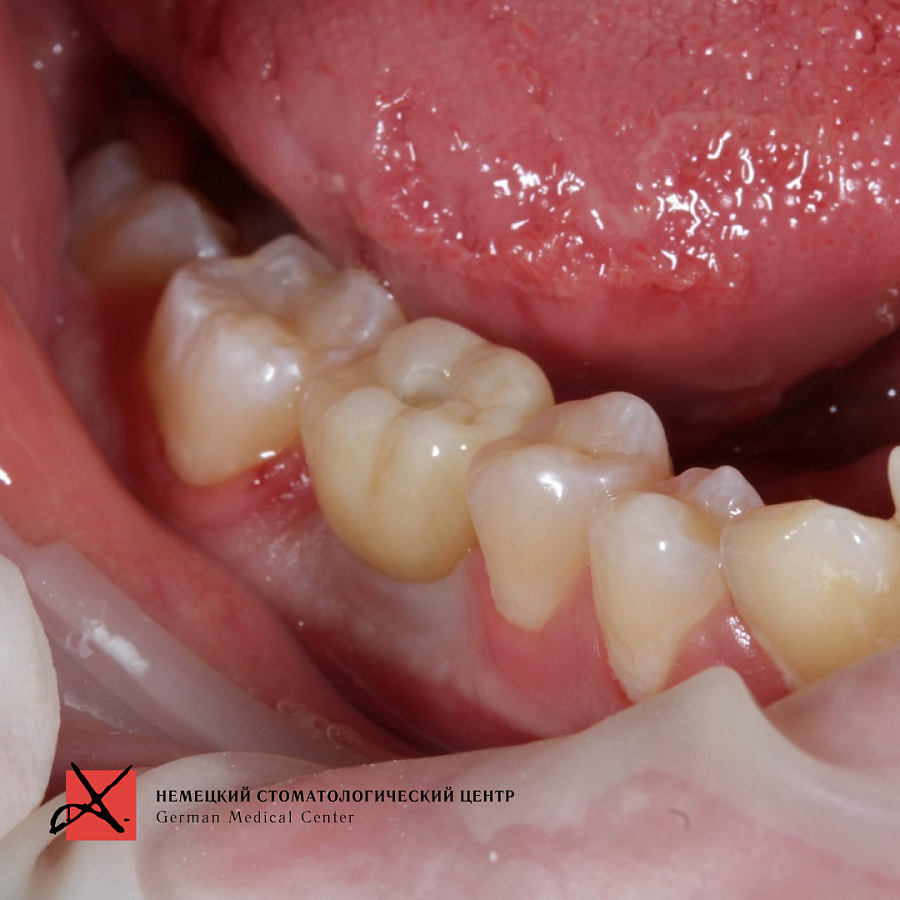

Зуб был фрагментирован, чтобы удаление прошло максимально атравматично, то есть без повреждения окружающих костных стенок. После удаления установлен имплантат. Операция прошла успешно, пациенту уже установлена зубная коронка.

Результат лечения